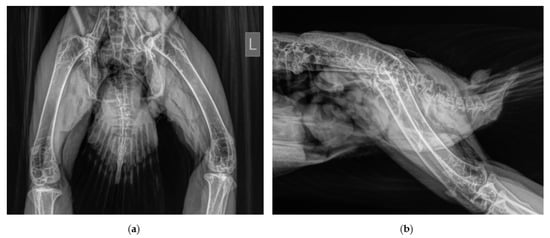

2.1. History and Clinical Examination